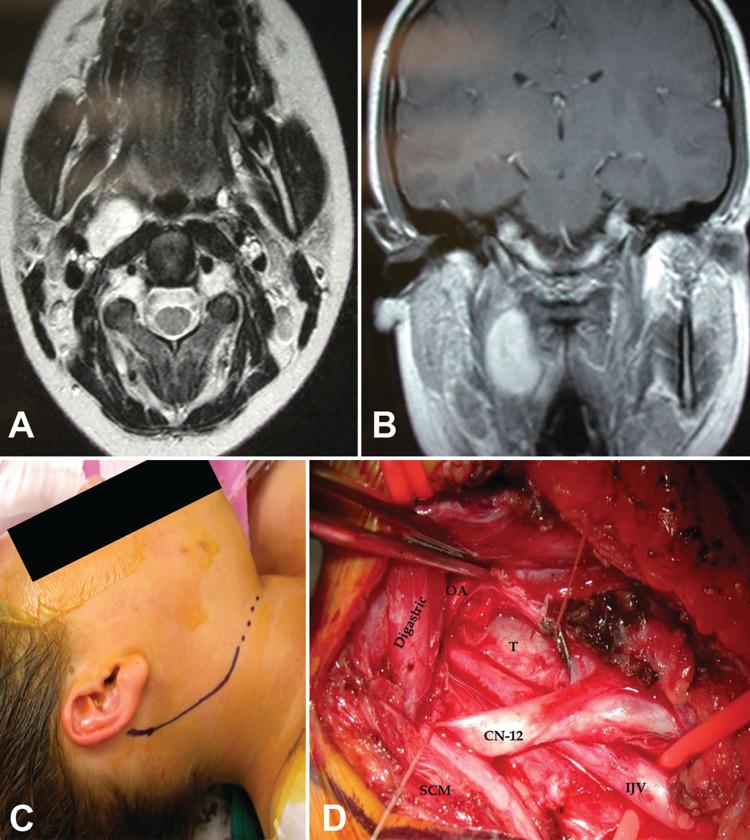

Introduction Lesions of the jugular foramen (JF) and postero-lateral skull base are difficult to expose and exhibit complex neurovascular relationships. Given their rarity and the increasing use of radiosurgery, neurosurgeons are becoming less experienced with their surgical management. Anatomical factors are crucial in designing the approach to achieve a maximal safe resection. Methods and methods Six cadaveric heads (12 sides) were dissected via combined post-auricular infralabyrinthine and distal transcervical approach with additional anterior transstyloid and posterior far lateral exposures. Contiguous surgical triangles were measured, and contents were analyzed. Thirty-one patients (32 lesions) were treated surgically between 2000 and 2016 through different variations of the retro-auricular distal cervical transtemporal approaches. Results We anatomically reviewed the carotid, stylodigastric, jugular, condylar, suboccipital, deep condylar, mastoid, suprajugular, suprahypoglossal (infrajugular), and infrahypoglossal triangles. Tumors included glomus jugulare, lower cranial nerve schwannomas or neurofibromas, meningiomas, chondrosarcoma, adenocystic carcinoma, plasmacytoma of the occipitocervical joint, and a sarcoid lesion. We classified tumors into extracranial, intradural, intraosseous, and dumbbell-shaped, and analyzed the approach selection for each. Conclusion Jugular foramen and posterolateral skull base lesions can be safely resected through a retro-auricular distal cervical lateral skull base approach, which is customizable to anatomical location and tumor extension by tailoring the involved osteo-muscular triangles.

对6具尸体头部(12侧)采用耳后迷路下和经颈远侧联合入路,并附加经茎突前方和远外侧后方暴露进行解剖。测量相邻手术三角并分析其内容物。2000年至2016年间,通过耳后远侧颈颞下入路的不同变体对31例患者(32个病变)进行了手术治疗。